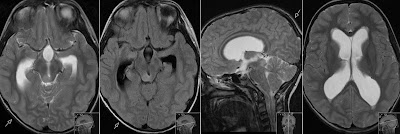

Short CaseTectal plate GliomaEdited By Professor Yasser Metwally

Figure 1. Precontrast MRI T1 images showing an isointense tectal plate glioma. The tumor is showing posterior exophytosis to the left side of the quadrigeminal cistern. ... Read Document